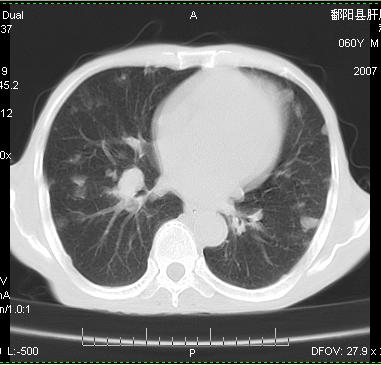

标题: CT12370:男.60岁.咳嗽发热胸痛. [打印本页]

标题: CT12370:男.60岁.咳嗽发热胸痛.

两肺示有散在大小不等类园形边缘不整密增高影.

考虑多发性转移瘤.请各位老师指导.

两肺及胸膜多发性转移瘤。

多发肺转移瘤及胸膜转移。

两肺及胸膜多发性转移瘤。纵隔淋巴结转移.

从病人年龄及肺内表现首先考虑转移瘤,但病人以咳嗽发热胸痛为首发症状还要考虑血行播散型肺脓肿及白血病非内表现等,结合实验室检查有鉴别意义。